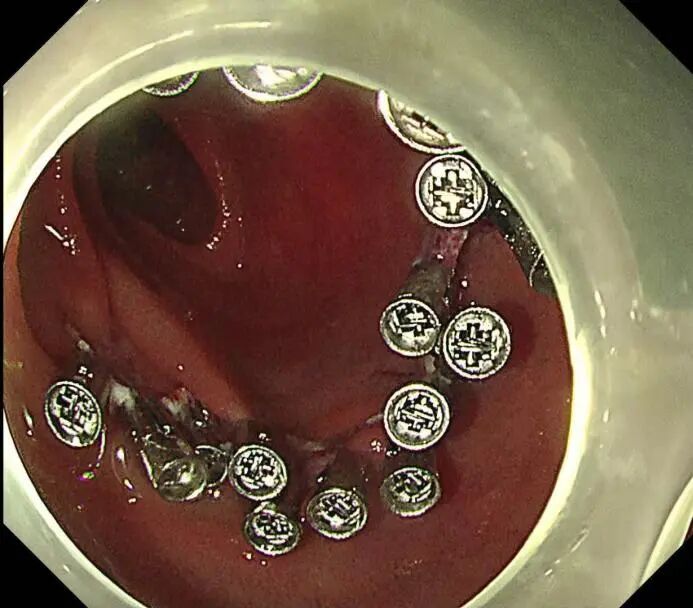

手术开始,尽管十二指肠降部空间有限,病变较大,且十二指肠部位血供丰富,但在SPEED技术的辅助下,徐美东教授用稳定的控镜和精妙的微操,如“庖丁解牛”般逐步推进,边注射边剥离,全程视野清晰可见,最终仅耗时半小时将该病变整体剥离并完整取出,完成这场“刀尖上的舞蹈”。创面干净、几乎无出血,没有丝毫肌层损伤,堪称内镜手术的“完美范本”。

5-金属夹闭合创面